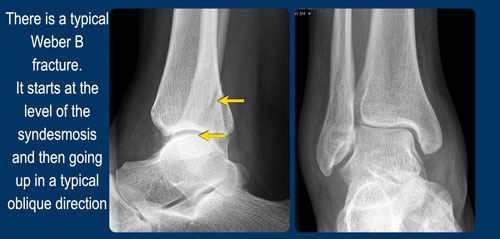

Đây có phải là gãy xương Weber type B không?

Đường gãy chéo ở vị trí ngang khớp chày mác (syndesmosis) thường dễ dàng phát hiện trên phim X-quang.

Các giai đoạn của Weber B

- Gãy xương mác chéo ở vị trí ngang khớp chày mác.